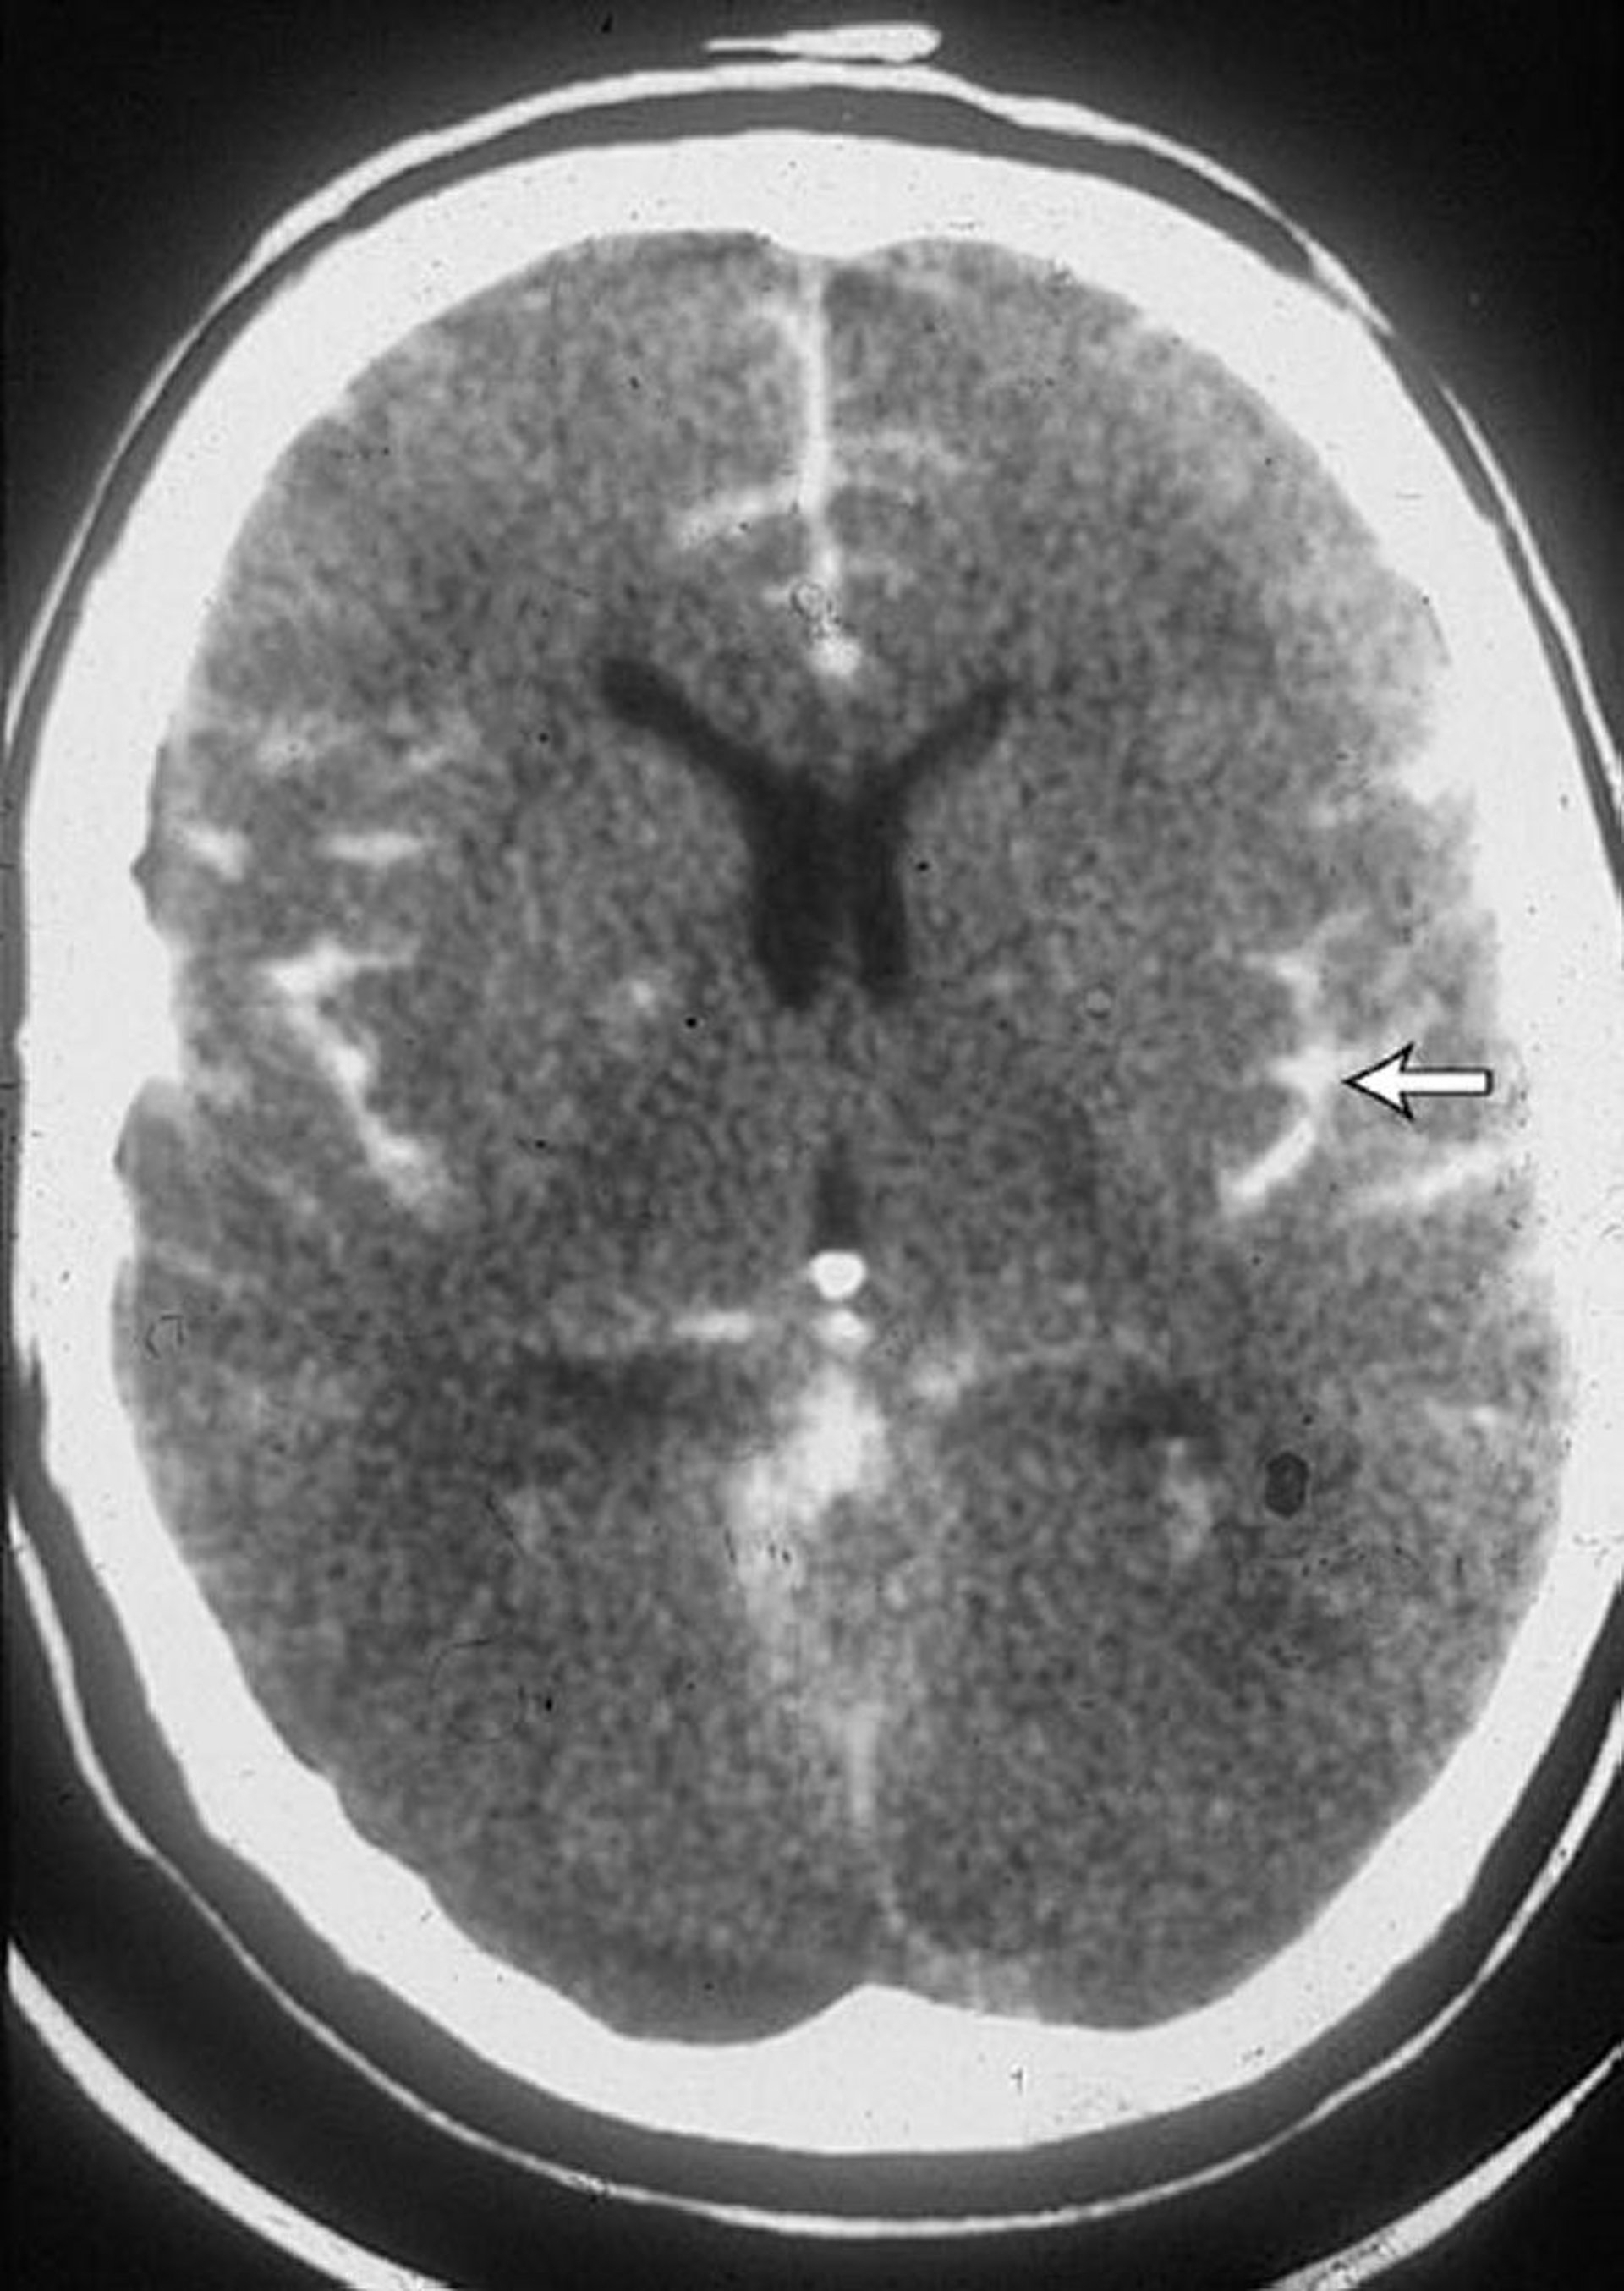

Hemorragia subaracnoidea

Esta TC en un paciente con una hemorragia subaracnoidea muestra sangre en los surcos (flecha). A menudo, se observa sangre en los ventrículos.

By permission of the publisher. From Lenaerts M, Couch J. In Atlas of Clinical Neurology. Edited by RN Rosenberg. Philadelphia, Current Medicine, 2002.